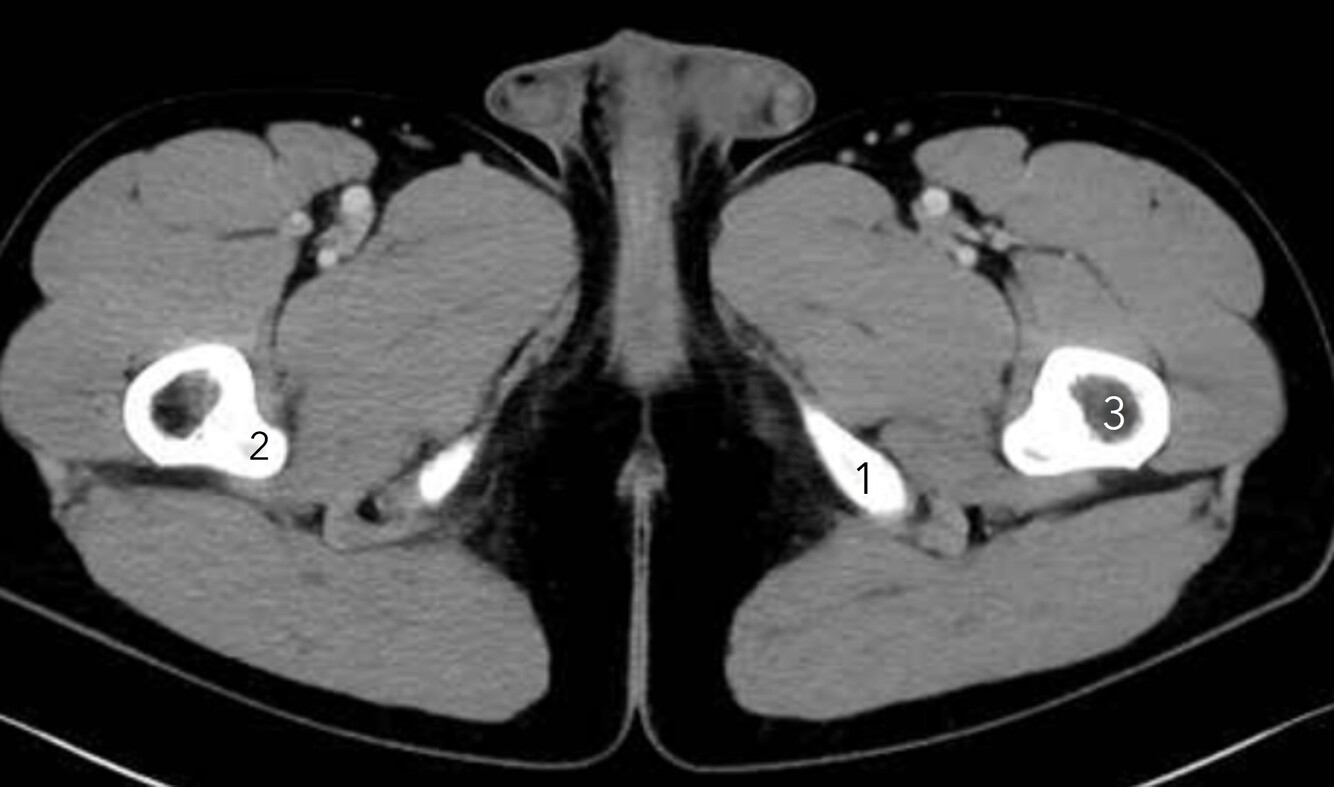

16

Q

Label 1-3

A

1. Lt inferior pubic ramus

2. Lesser trochanter (Rt femur)

3. Lt femur